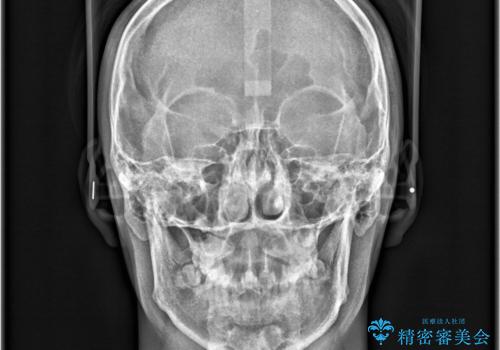

- 「歯のでこぼこを治したい 1年くらいで矯正を終わらせたい」を主訴に来院された患者様です。

叢生量は多く無く歯の傾斜も標準傾斜だったので歯は抜かずにワイヤー矯正で治療を行いました。

左側は2級傾向が強く臼歯の遠心移動をご提案しましたが、1年以内に矯正を終わらせたいという患者様のご意向で希望されず叢生を改善する矯正となりました。